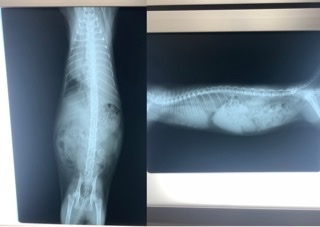

最初に熱を測ってもらった所40.3℃と高熱で、呼吸数が異常に速く感じていた事もありレントゲンもとって頂きました。

その時とって頂いたレントゲンになります。

レントゲンを確認した先生から、非常に危険な状態かもしれない。。。胸の辺りに水が溜まってるかも。。。うちではこれ以上は診れないから、紹介する病院に今直ぐ連れて行ってくださいと言われました。

再度レントゲンをとって頂き確認してもらった所、胸水が溜まっていました。

胸水が溜まっている為心臓が圧迫されて呼吸が速かったと。